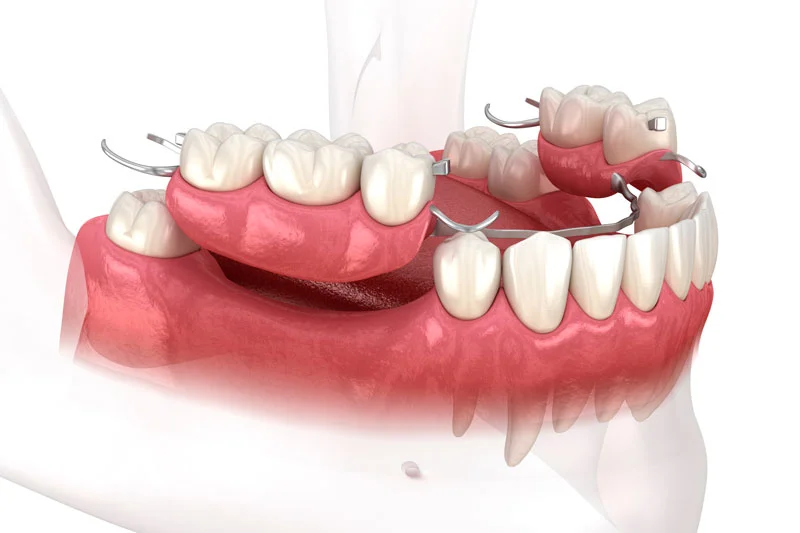

Couronnes, bridges et prothèses sur mesure pour un résultat naturel et durable.